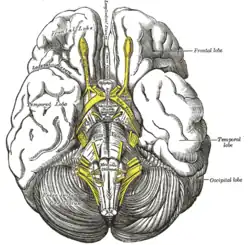

Base of brain (Tuber cinerum visible at center). | |

The tuber cinereum is a hollow eminence of the middle–ventral hypothalamus, specifically the arcuate nucleus, situated between the mammillary bodies and the optic chiasm. In addition to the ventral hypothalamus, the tuber cinereum includes the median eminence and pituitary gland.[1] Together with the hollow itself, it is sometimes referred to as the pituitary stalk.

Structure

The tuber cinereum is an inferior distention of the floor of the third ventricle; the conical hollow formed by the distention (a continuation of the ventricle itself), is known as the infundibulum (funnel).[1] Thus, the tuber cinereum is anteriorly continuous with the lamina terminalis, while laterally it is continuous with the anterior perforated substances of the hypothalamus. The inferior end adjoins the posterior lobe of the pituitary gland.